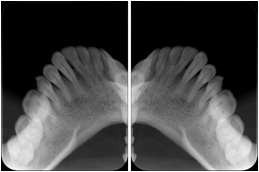

3. A dental provider wishes to capture a series of DICOM IO images for the patient’s dentition. The tooth morphology, teeth are divided into molars, premolars, canines and incisors, and a number of images for each jaw. The anatomic information was captured utilizing the triplet of schema. This standard code sequence is based on ISO 3950-2010, Dentistry - Designation system for teeth and areas of the oral cavity.

Every IO image should have anatomic information either through the primary or modifier sequence.

In most standard cases, images are oriented in structured layouts. These structured displays are useful to be shared between providers for reference purposes.

Table OO.1.1-1 shows structured display standard templates, where Viewset ID is based on the Japanese Society for Oral and Maxillofacial Radiology (JSOMR) classification provided by JIRA (Japan Medical Imaging and Radiological Systems Industries Association, www.jira-net.or.jp). Expected or typical teeth to be imaged location, region and designation codes are based on ISO 3950-2010, Dentistry - Designation system for teeth and areas of the oral cavity. For all the hanging protocols listed in OO.1.1-1, the value to use for Hanging Protocol Creator (0072,0008) is "JSOMR" and the value to use for Hanging Protocol Name (0072,0002) does not include "JSOMR" (e.g., "DL-S001A", not "JSOMR DL-S001A").